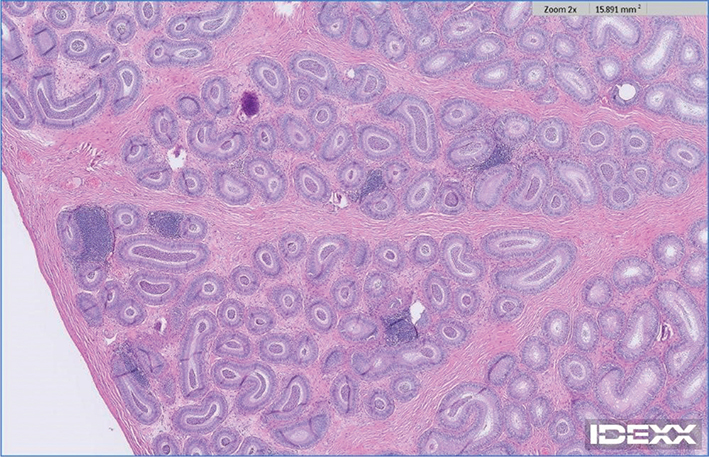

Case 1: A 3½ year, intact male Treeing Walker Coonhound, was presented for ultrasonographic evaluation of the abdomen and testes due to weight loss and polyphagia in July of 2021. Semen had not been evaluated, but the dog had sired a litter in 2020. Left testis appeared normal and had a coarse medium echogenicity throughout; right testis contained hyperechoic foci that were slightly larger than typical testicular microliths observed in human beings but were identical to TM in all other aspects (Figure 1). Other findings on abdominal ultrasonography included a complex cystic structure in the right kidney. Ultrasonography of the testes was repeated in October of 2021 and July of 2022, with no changes noted from the original ultrasonography. In October of 2022, the dog was castrated, due to concern about testicular microlithiasis, a couple of episodes of prostatitis, and retirement from breeding. Right testis was submitted for histopathology; 2 discrete and relatively small foci of intratubular mineralization accompanied by surrounding fibrosis were noted. In these foci, aggregates of fragmented basophilic material, interpreted to represent mineralization, were present within shrunken seminiferous tubules surrounded by a moderate amount of fibrosis (Figures 24) without associated inflammation.

Figure 1.

Figure 1. Testicular ultrasonographic image of Case 1